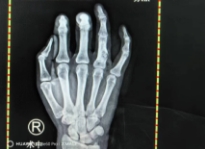

术前X光片

肿物刮擦+植骨后手部X线